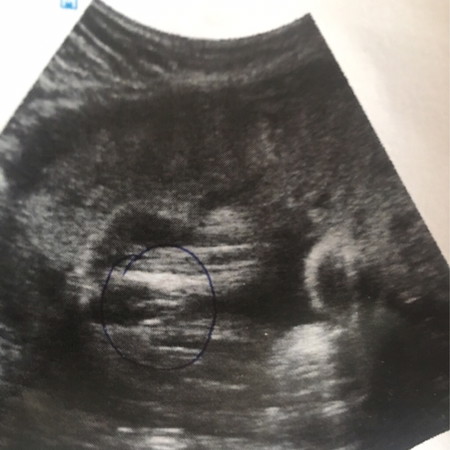

เพศ

ชายหรือหญิงนร้าา ดูออกมั้ยค่ะ

ดูไม่ออกเหมือนกันค่ะ